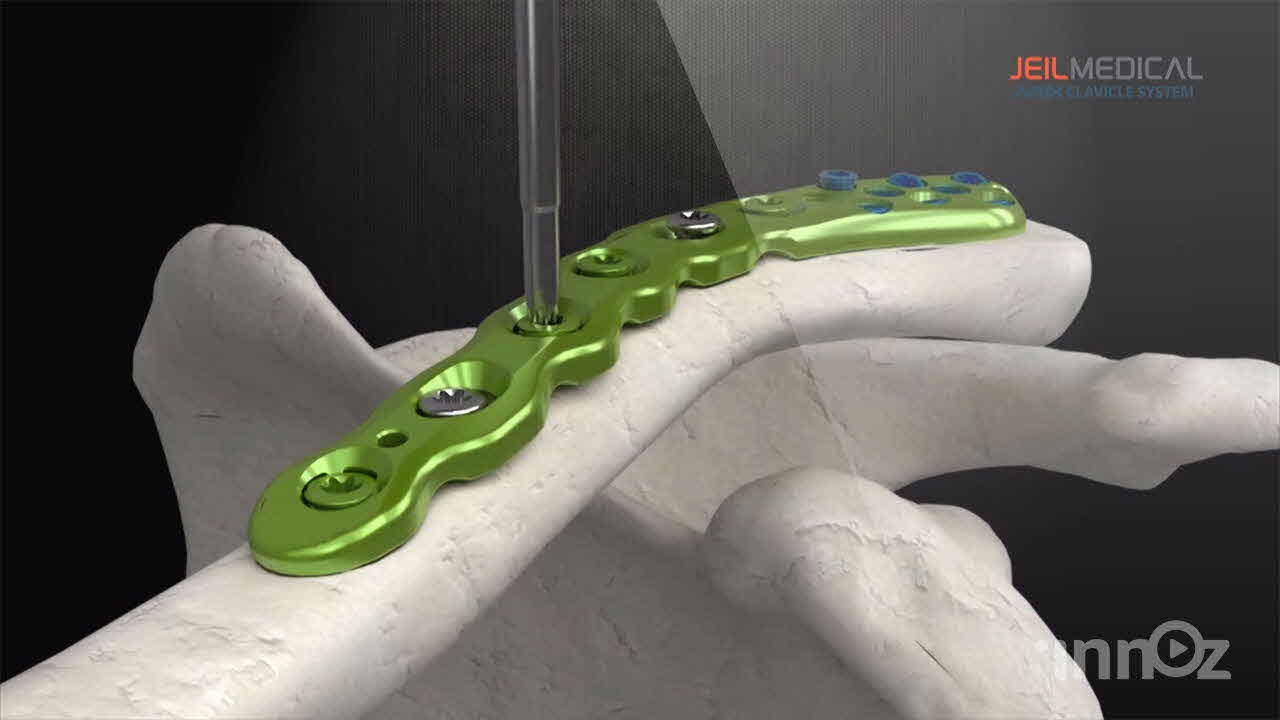

제일메디칼

제일메디칼

제일메디칼

제일메디칼

제일메디칼